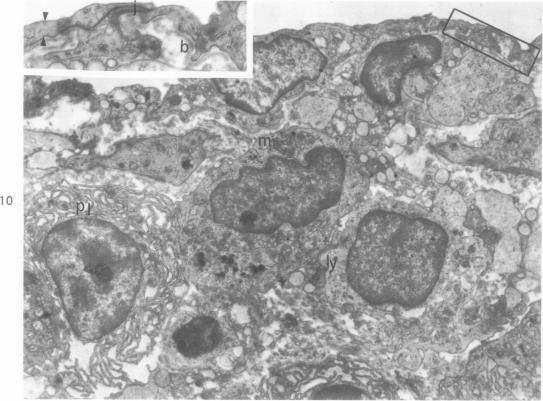

Thickening of arterial intima in rat cardiac allografts. A light and electron microscopic study.

Am J Pathol. 1971 Apr;63(1):69-84.